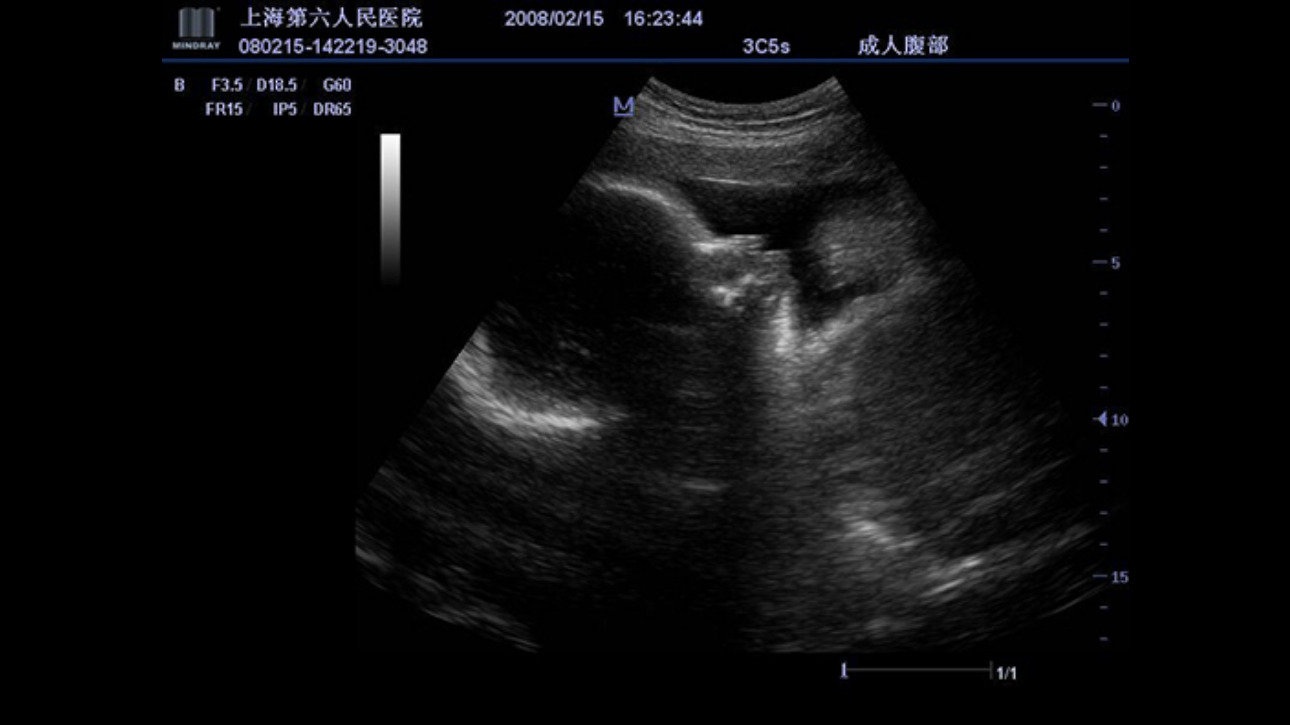

A fully-featured laptop style color Doppler system, M5 offers uncompromised 2D performance and exceptional value in a highly convenient and easy to use package. The portable, simplistic nature of the M5 makes it ideal for a variety of hospital and office environments.

Get a complete and extended view of the anatomical structure through panoramic imaging, coupled with velocity indication and forward/backward scan ability making scanning much easier, smoother and more controllable.

ExFOV

Discover better diagnostic information through extended view of the anatomical structure on all convex and linear probes.